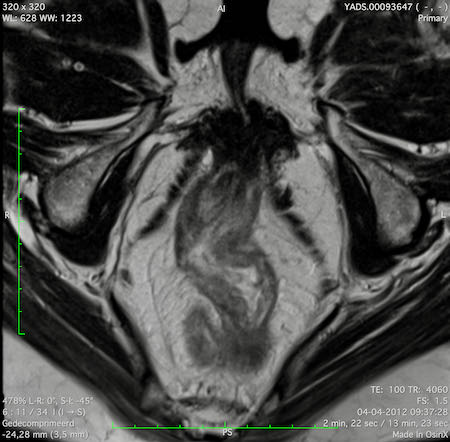

Đặc điểm MRI

- Thường khó xác định

- Thường biểu hiện nhưdày thành ruột lan tỏa, đoạn dài

- Kiểu tăng trưởng dưới niêm mạc, cho ra mộtHình ảnh “bia” (target)trên các hình ảnh cắt ngang

- Thâm nhiễm mỡ trực tràng lan tỏalà phổ biến

Hình ảnh

Các hình ảnh được cung cấp cho thấy ung thư biểu mô tế bào nhẫn với tình trạng dày lan tỏa thành trực tràng, hình ảnh bia bắn điển hình, và sự xâm lấn mỡ mạc treo trực tràng.